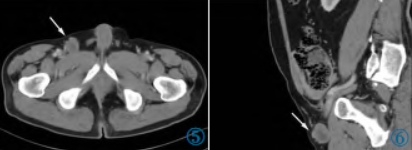

2 年前患者因发现右侧腹股沟区包块12 天再次入院。查体右侧腹股沟区可见触及肿物大小约3 cm×2 cm,质韧,边界尚清楚,活动度较差。腹部CT 增强(图4~6)示右侧腹股沟区可见类圆形软组织结节,大小约2.8 cm×2.3 cm,边缘尚清楚,平扫CT 值约31 HU,增强扫描静脉期CT 值约40 HU,肿物强化不明显,中央呈相对低密度。行超声引导下穿刺活检术,病理诊断为胃肠间质瘤(Gastrointestinal stromal tumor,GIST)。

图4~6 腹部CT 平扫轴位、静脉期轴位及矢状位图像示右侧腹股沟区类圆形软组织结节。

免疫组化结果:CD117(+),DOG-1(+),Vimentin(+),CD34(+),Ki-67(阳性细胞数40%)图(7,8);基因检测结果:c-kit 基因11 外显子点突变。遂继续予以口服甲磺酸伊马替尼(格列卫)400 mg/d,服药后肿物逐渐缩小至稳定,1 年前腹部CT 平扫(图9)示大小约2.4 cm×1.7 cm。